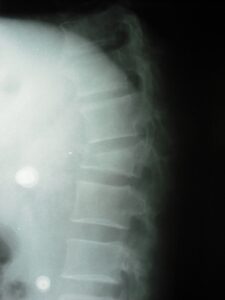

Fratura torácica com cifose importante.

A grosso modo existem dois grandes grupos de fratura, as relacionadas a traumas de alta energia – geralmente acidentes automobilísticos ou quedas de grandes alturas – e as relacionadas a traumas de baixa energia – normalmente presentes em pacientes com osteoporose ou com tumores na coluna, acontecendo em quedas simples, em casa, ou até ao sentar-se ou virar-se bruscamente na cama.

O risco maior destas fraturas é o de dano neurológico, pela proximidade dos fragmentos das vértebras fraturadas da medula e de outras estruturas nervosas, podendo levar a sequelas graves e muitas vezes irreversíveis. Além disso a deformidade causada pela fratura pode levar a dor crônica, se não for adequadamente tratada, no momento certo.

A maioria das fraturas sem comprometimento neurológico, e com deformidades menores, podem ser estabilizadas através da técnica cirúrgica de CIFOPLASTIA, mas muitas vezes quando há deformidade maior, ou compressão nervosa, fica indicado o tratamento de CIRURGIA CORRETIVA PARA FRATURAS DA COLUNA.